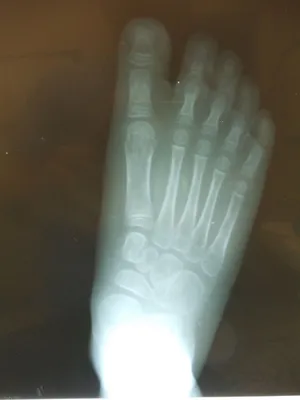

Pre-operative x-rays of the flatfoot with the talus deviated medially due to subluxing off the calcaneus causing the midtarsal joint to sublux laterally and uncovering of the talar head at the talo-navicular joint (left). The talus bone should line up with or be close to paralletl with a line drawn through the 1st metatarsal shaft (right). This is referred to as Meary's angle.

One case see an improvement in Meary's angle after surgical repair of the flatfoot with a subtalar joint implant which blocks the subluxation of the talus off of the calcaneus.